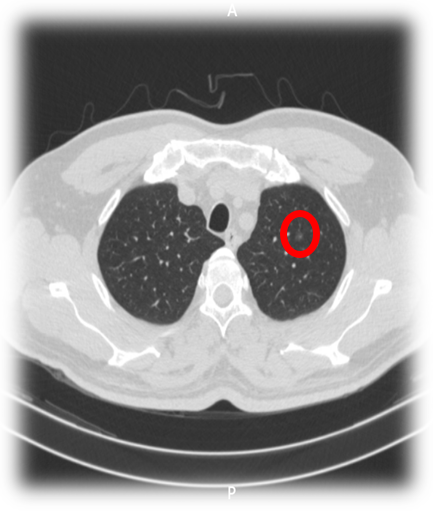

▲左上肺结节右肺术后1月行微波消融(MWA)治疗

MWA治疗过程及效果:

治疗效果理想: